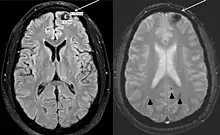

- 1 2 3 Lizarraga, Karlo J; De Salles, Antonio AF (20 September 2011). "Multiple cavernous malformations presenting in a patient with Poland syndrome: A case report". Journal of Medical Case Reports. 5 (1): 469. doi:10.1186/1752-1947-5-469. PMC 3195104. PMID 21933407.